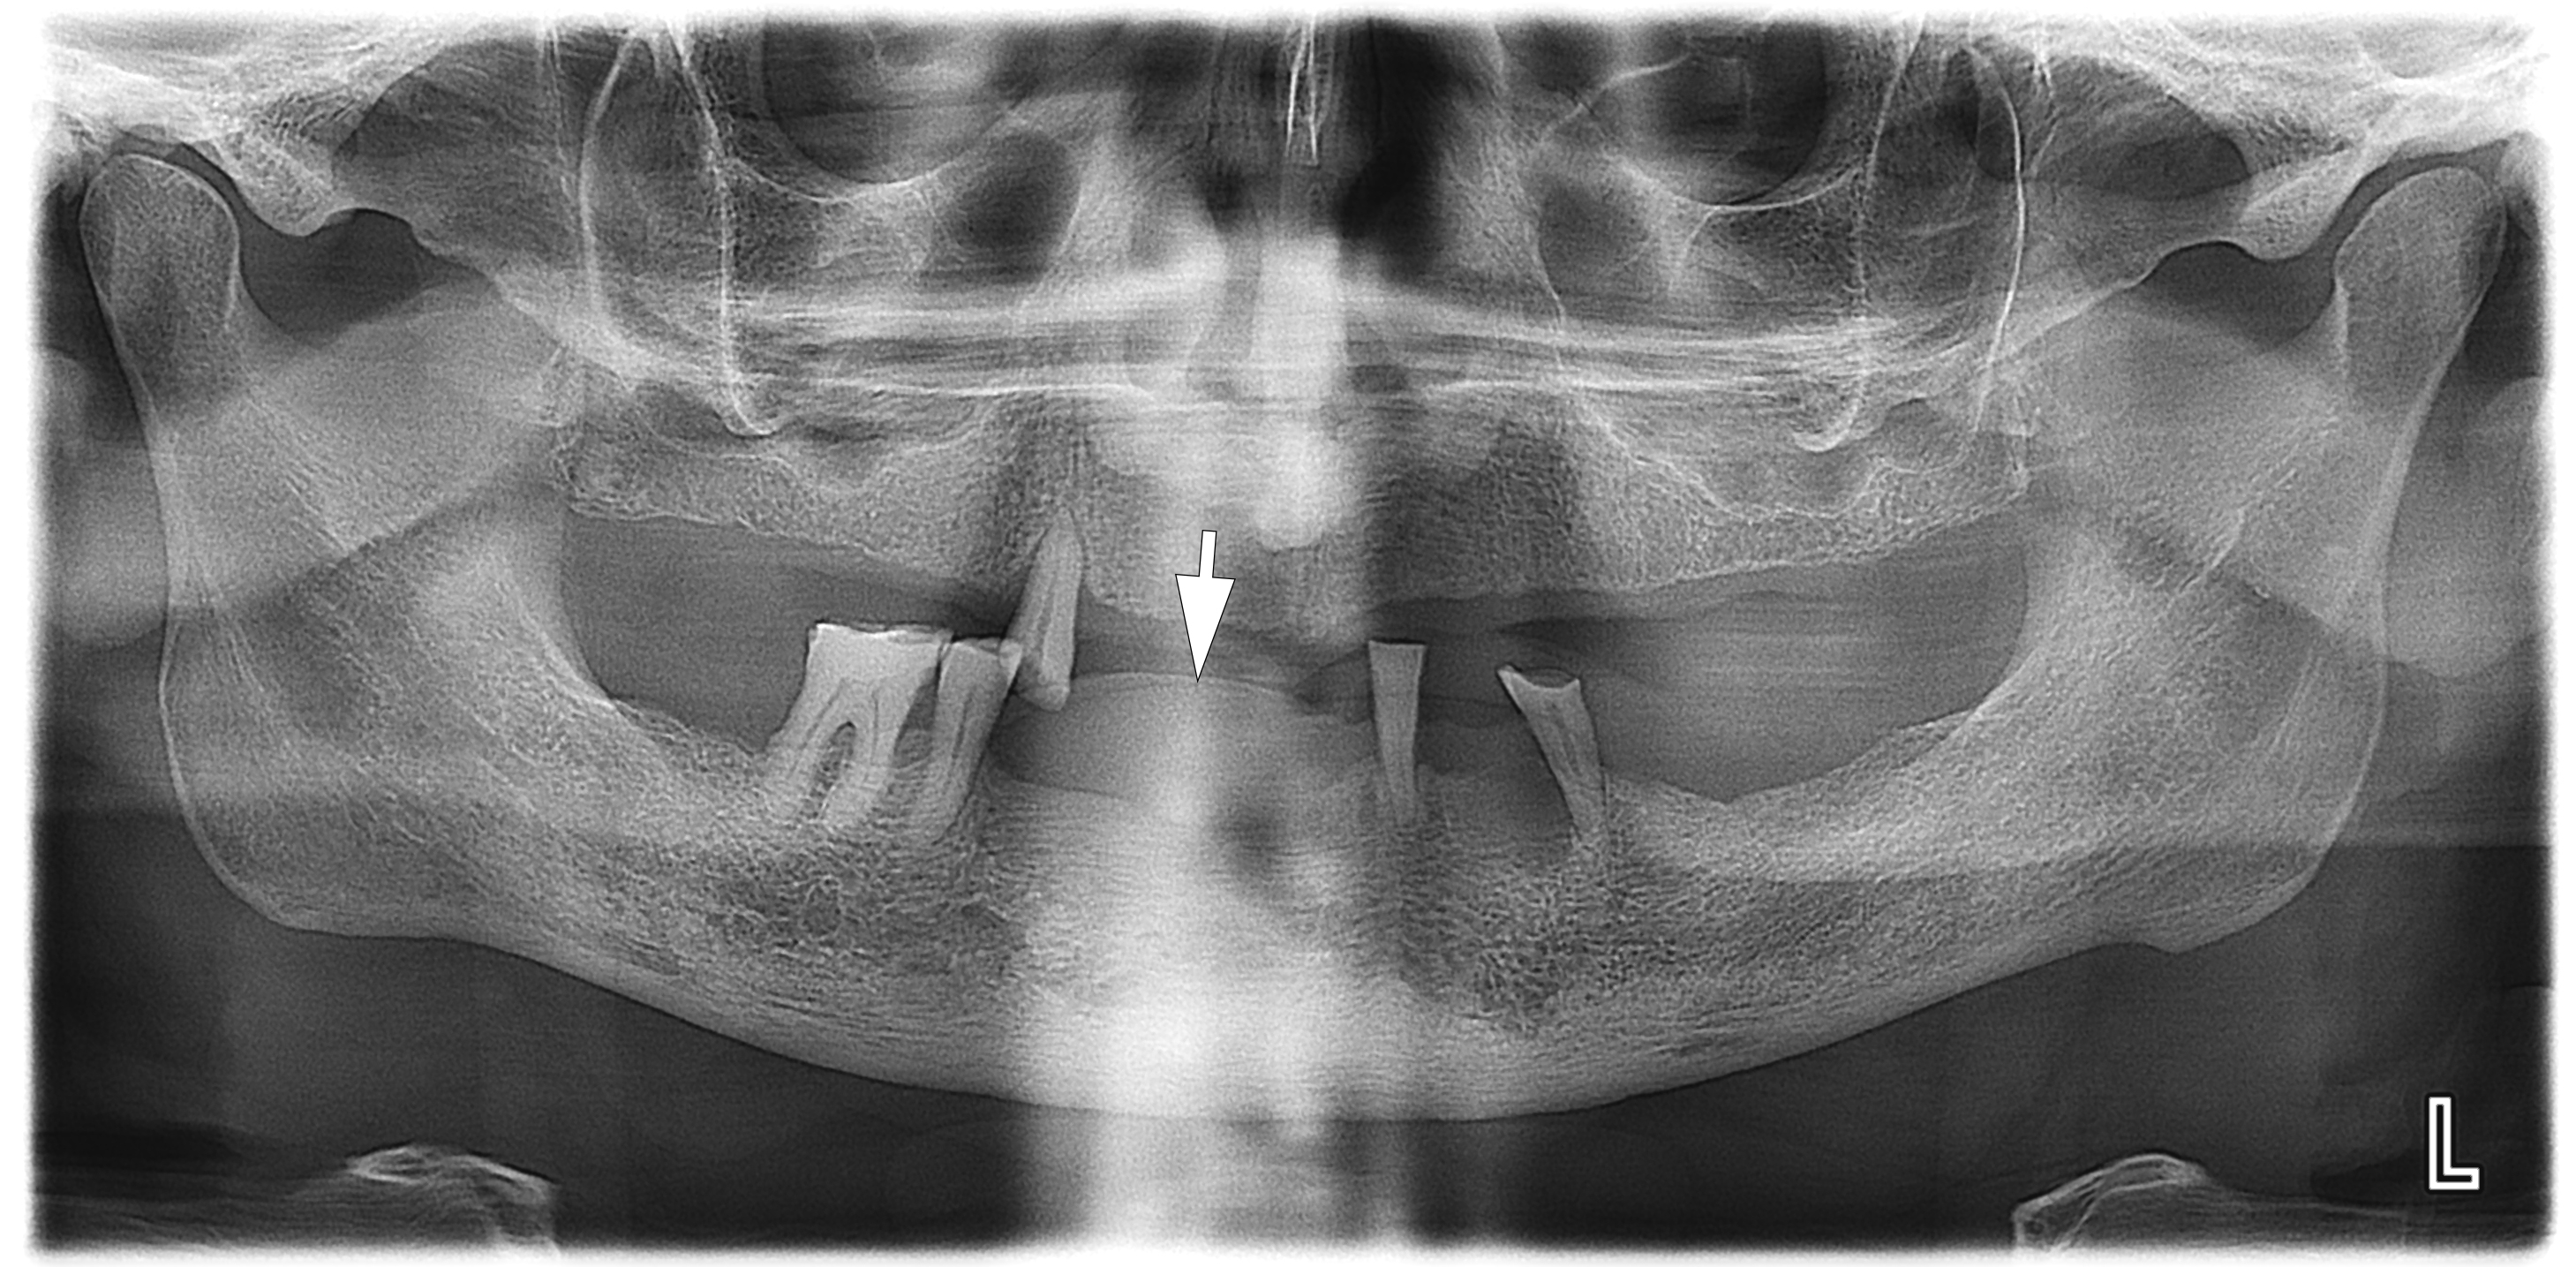

A radiographic examination was performed to assess the condition of the bone tissue and teeth, and an USG was performed to assess the structure and vascularization of the soft tissue lesion. The panoramic radiograph (Fig 2) showed a dome-shaped radiopacity rising above the alveolar ridge of the edentulous area of the anterior mandible.

The simplest method of diagnosing the oral cavity is panoramic radiography. It is also appropriate in the case of PGCG, but it solves a limited range of issues, namely, assessing the condition of neighboring teeth and the presence of bone resorption.

In our case, it was difficult to reliably determine the areas of ossification in the projection of radiopacity (i.e., PGCG) on the orthopantomography. This can most likely be explained by an insufficient level of ossification. In other cases, newly formed bone tissue in the projection of the PGCG was visible radiologically [23].